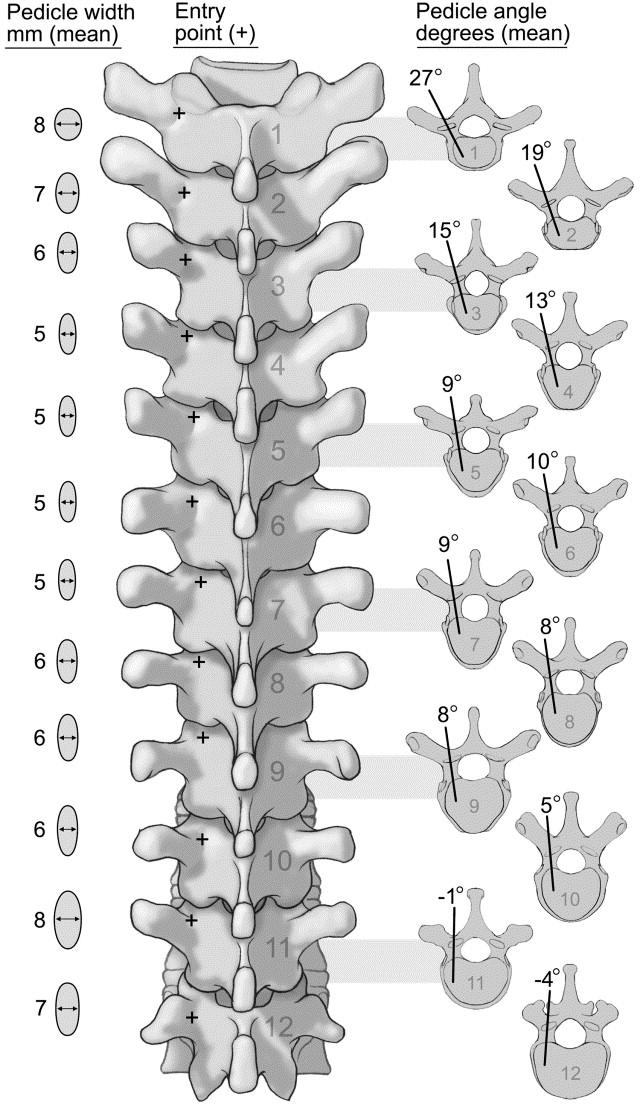

Entrypointsvarybasedonlocation

Lumbar: Confluenceofanyof:Parsinterarticularis,Mamillaryprocess,Lateralborderofsuperiorarticularfacet,Mid TransverseProcess

Thoracic: 2mm lateral and caudal to the intersection of the mid portion of facet joint and superior edge of transverseprocess.Movesmoresuperiorlywithhigherthoraciclevels

Cervical:2-3mmBelowinferioredgeofsuperiorfacet,5-6mmmedialtolateraledgeoflateralmass

B C D 10

Figure 6: Anatomical Variations in Entry Points of Pedicle Screw Fixation. A) General Entry points for axial/sagittal trajectoriesateachspinallevel,B)LumbarSpineRelevantAnatomy(targetshighlightedinpurple/pink),C)OptimalAngles usedforThoracicSpinePedicleScrewFixation,D)CervicalSpinePedicleScrewFixationtrajectory